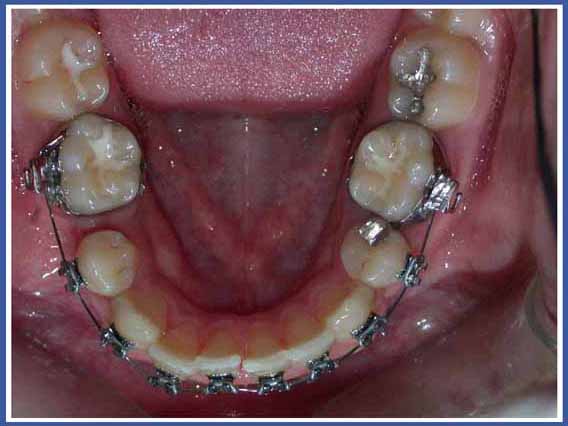

שומר המקום הינו מתקן מתכתי קטן אשר מוכן ומותאם במיוחד לפה של הילד שלך. הוא מקובע באופן יציב בפה ויוסר כאשר השן קבועה בעמדתה הנכונה. המתקן בנוי בדרך כלל מטבעת מתכת המודבקת לשן סמוכה וחוט מתכת שמחובר אליה ונשען על שיניים סמוכות. מטרת המכשיר לייצב את השיניים הנותרות מכל צד של המרווח ולמנוע מהן לזוז לכיוון המרווח עד לבקיעת השן הקבועה לעמדתה התקינה.